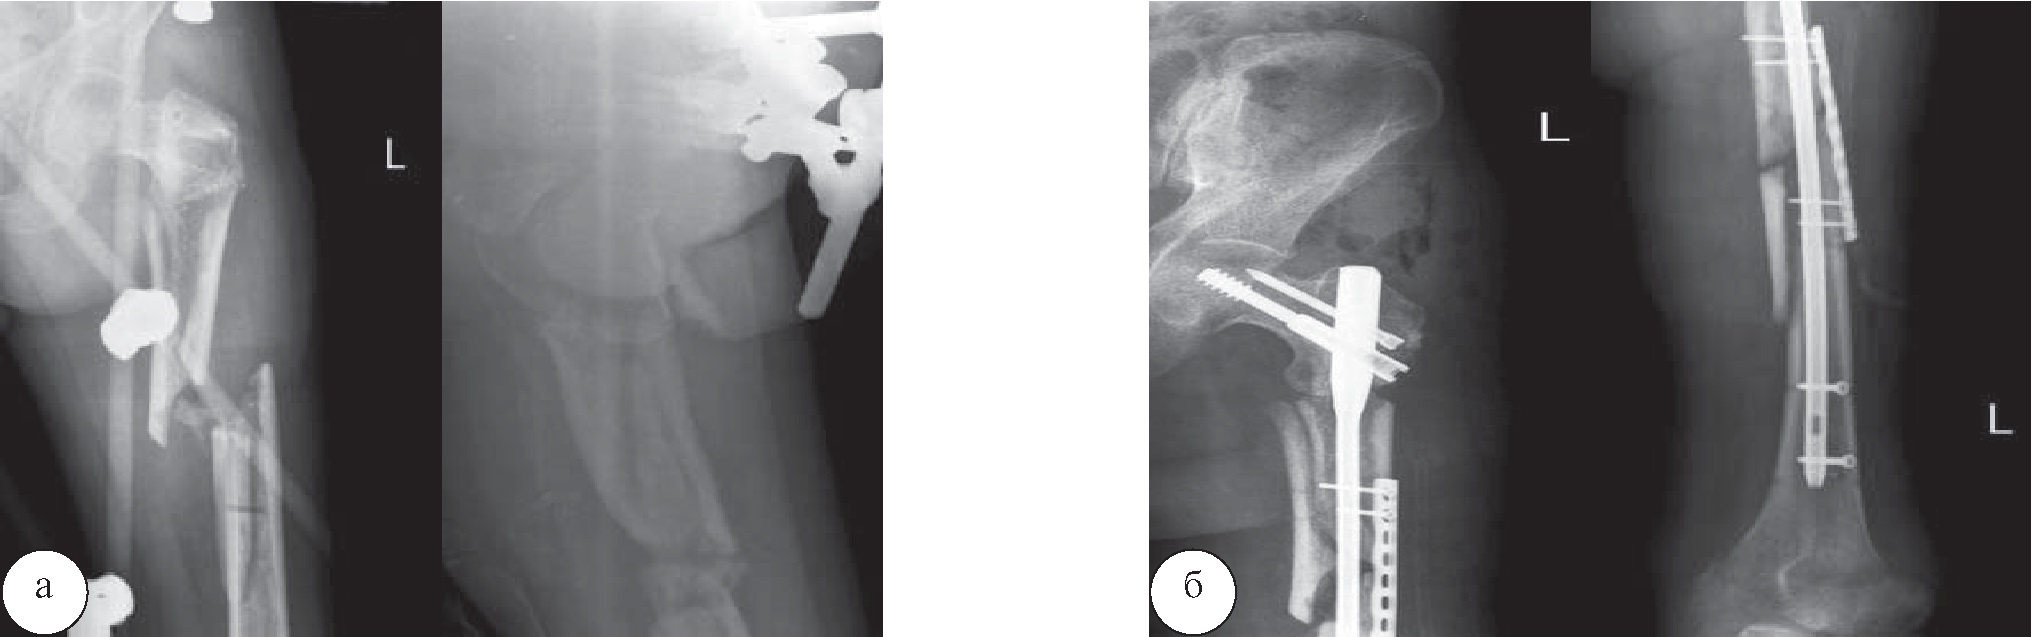

Рис. 4. Рентгенограммы левой бедренной кости пациента М.: а – неправильно срастающийся фрагментарный перелом верхней трети левой бедренной кости, фиксированный стержневым аппаратом внешней фиксации; б – после операции – остеосинтеза интрамедуллярным гвоздем с блокированием и аугментацией пластиной

Рис. 5. Рентгенограммы левого плеча и предплечья пациента Р.: а – огнестрельный внутрисуставной многооскольчатый перелом дистального метаэпифиза плечевой кости, проксимального метаэпифиза костей предплечья, фиксированный стержневым аппаратом внешней фиксации; б – после операции – последовательного остеосинтеза плечевой кости двумя пластинами, локтевой кости – пластиной